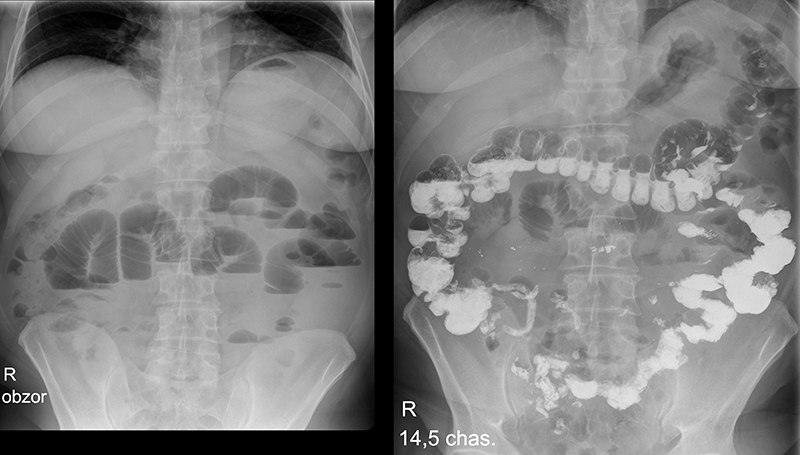

Данные инструментальных методов диагностики не являются особенно информативными, но их привлекают для комплексного диагностического процесса – больше для дифференциальной диагностики. Применяют такие методы, как:

- рентгенография пассажа бария по тонкому кишечнику – больному предлагают выпить порцию сульфата бария и через полчаса проводят рентгеноскопию и -графию кишечника. Во время исследования можно выявить участки спазма подвздошной кишки и нарушение пассажа (перемещения) сульфата бария – замедленное опорожнение подвздошной кишки от контрастного вещества. В тяжелых случаях возможны признаки динамической (из-за нарушения моторики кишки) кишечной непроходимости – в частности, отсутствие пассажа бария;